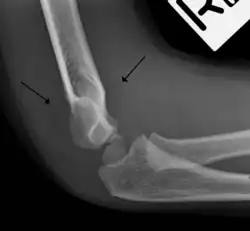

The fat pad sign, also known as the sail sign, is a potential finding on elbow radiography which suggests a fracture of one or more bones at the elbow. It may indicate an occult fracture that is not directly visible. Its name derives from the fact that it has the shape of a spinnaker (sail).[1] It is caused by displacement of the fat pad around the elbow joint. Both anterior and posterior fat pad signs exist, and both can be found on the same X-ray.

In children, a posterior fat pad sign suggests a condylar fracture of the humerus. In adults it suggests a radial head fracture.

The fat pad sign is invaluable in assessing for the presence of an intra-articular fracture of the elbow. An anterior fat pad is often normal. However a posterior fat pad seen on a lateral x-ray of the elbow is always abnormal. The patient will be unable to flex their elbow and requires orthopaedic input.[2]

The posterior fat pad is normally pressed in the olecranon fossa by the triceps tendon, and hence invisible on lateral radiograph of the elbow.[3] When there is a fracture of the distal humerus, or other pathology involving the elbow joint, inflammation develops around the synovial membrane forcing the fat pad out of its normal physiologic resting place. This is visible as the "posterior fat pad sign" and is often the only visible marker of a fracture, particularly in the pediatrics population.